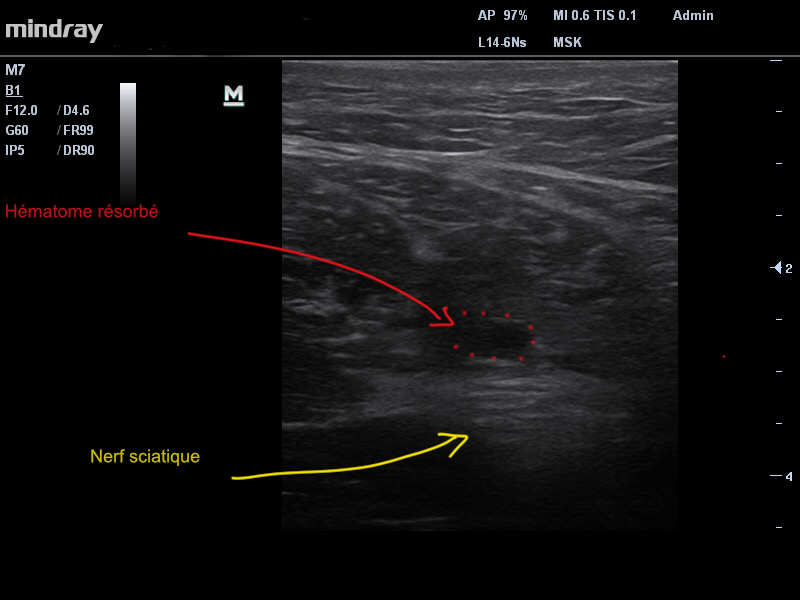

Un traitement par Ondes de Choc de faible puissance , a également été appliqué afin de favoriser les mécanismes de proliferation necessaires à la cicatrisation musculaire. Le port d’un cuissard de compression a été recommandé. La prise d’anti-inflammatoires a été proscrite. Cinq semaines après la première échographie, le patient présente une nette évolution clinique ainsi qu’à l’imagerie et commence une petite réhabilitation pour réadapter le muscle à l’effort (image 2).

Image 2. Après 5 semaines d”évolution. Nette résorption de l’hématome , cicatrisation des fibres. Le nerf sciatique n’est plus refoulé.